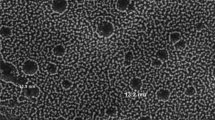

Photodynamic inactivation at a concentration of 50 µM EB (without acetic acid) was ineffective against all tested A. baumannii strains (in planktonic form) and only caused less than 1 log10 CFU reduction in the number of viable bacteria. A. baumannii strains were not significantly affected by the PDI treatment even after the erythrosine concentration was raised up to 400 µM (without acetic acid). PDI with EB in 0.01% acetic acid (AA) showed promising results against planktonic cells of A. baumannii. As shown in Fig. 1, AA (0.01%) alone and in combination with EB (50 µM) in the dark caused less than 1 log10 CFU reduction in the number of bacterial cells in comparison with the untreated control while EB-mediated PDI under acidic condition caused a significant reduction in viable count of the tested strains (> 7 CFU/ml).

PSs bearing an anionic charge such as EB need agents that increase their penetration into the outer membrane of gram-negative bacteria. So we examine the effect of acetic acid (0.01%) on the erythrosine-mediated PDI of A. baumannii. The results showed the addition of acetic acid (0.01%) to EB, potentiated the PDI against A. baumannii cells. The planktonic cells of A. baumannii were almost eradicated by illumination in the presence of EB and AA. The mechanisms behind the additive effect of acetic acid on EB-mediated PDI are unknown. It seems that the low pH (pH < 3.5) associated with the presence of acetic acid can cause the formation of erythrosine monoanionic form that would be potentially more effective than dianionic form in the PDI efficacy of gram-negative bacteria [28]. In fact, the monoanionic form of erythrosine possesses a higher binding affinity to the bacterial outer membrane than dianionic form.